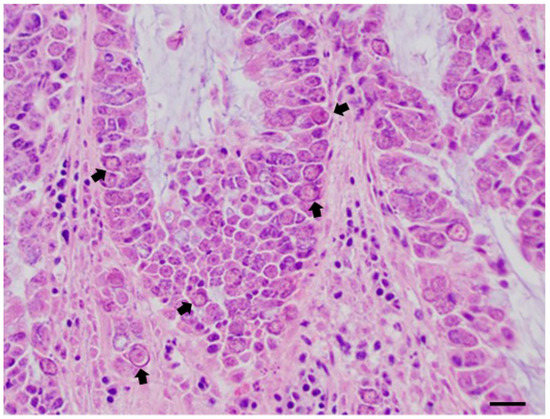

| Little owl 12 | Intestine | Capillaria tenuissima (Nematoda: Capillariidae) 4 * | - | Neodiplostomum attenuatum (Platyhel-minthes: Diplostomatidae) 10 * | - | Eumonosporamochogalegoi/Eumonospora henryae (Apicomplexa: Sarcocystidae) |